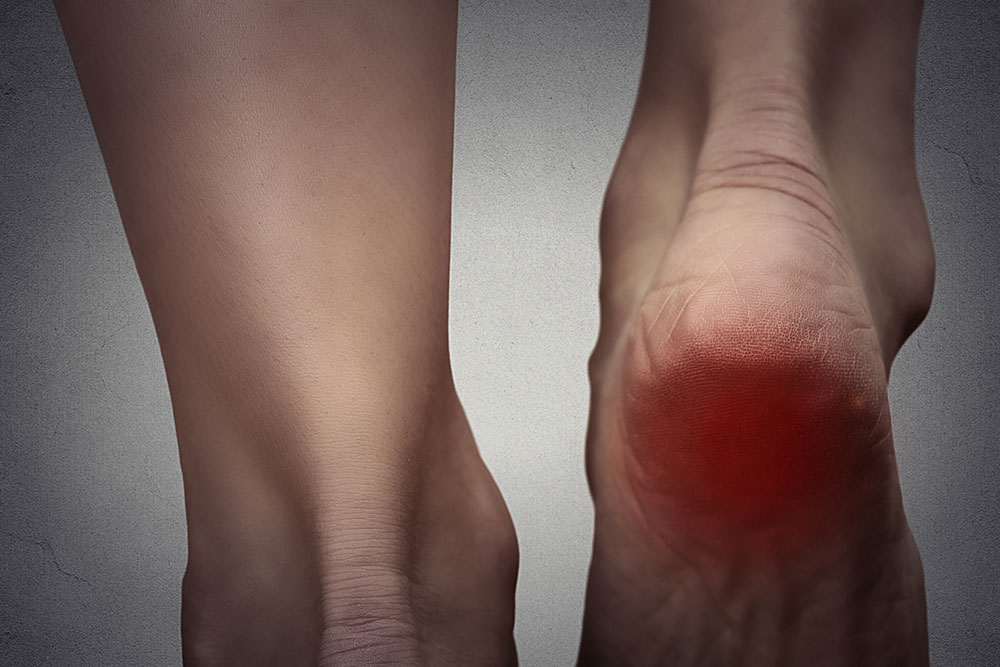

Being a chronic disorder, pain due to fibromyalgia can hit anywhere, at any intensity, and at any time.

- The soles feel like they are on fire, and these pains come and go at random intervals.

- Unable to touch bare feet on the floor without wearing slippers.

Experts believe that one in every four people who have fibromyalgia have foot pain, but many do not opt for treatment.